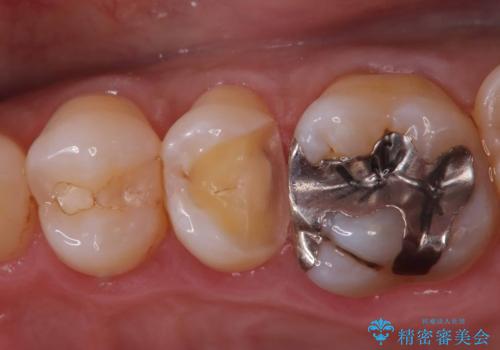

- 「フロスをしたら銀歯が取れた」を主訴に来院された患者様です。

レントゲン検査で虫歯が認められました。

古い材料を除去後、その下に大きな虫歯が広がっていました。

神経の近くまで虫歯が広がっていたため、虫歯の除去後、神経を保護する材料をおきセラミックインレーで治療を行いました。